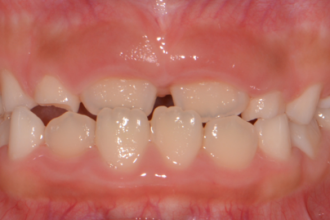

치아교정